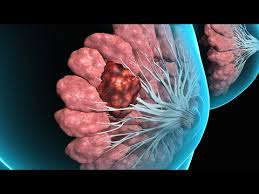

गाँठ

मन पर पड़े या तन पर

भुगतते हैं खामियाजे तन और मन दोनों ही

गाँठ पड़ती है कभी

गाँठ जीवन से जितनी जल्दी निकले

गांठ : मनके-सी!

गले में पड़े मनके की तरह

उग आई हैं गांठें।

छोले, राजमा, चने सी गाँठ!

उपमा देते हैं गांठों की

अक्सर खाद्य पदार्थों से

चने दाल सी, मटर के साइज सी

भीगे छोले या राजमा के आकार सी

छोटे, मझोले, बड़े साइज के आलू सी.